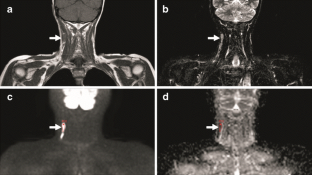

Fig. 2